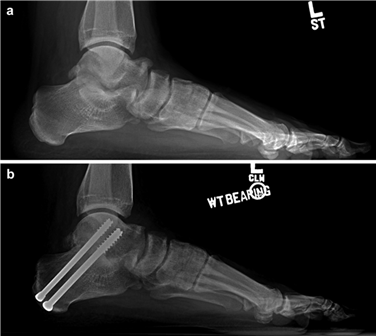

The Lapidus Arthrodesis (First TMT Fusion)

For severe deformities or hypermobility, the Lapidus procedure provides robust stabilization of the medial column. A dorsal or medial incision is utilized over the first TMT joint. The extensor hallucis longus (EHL) is retracted dorsally, and the tibialis anterior tendon is identified and protected at its insertion on the medial cuneiform and first metatarsal base. The TMT joint capsule is incised, and the joint is thoroughly debrided of all articular cartilage using a combination of osteotomes, curettes, and a high-speed burr.

To achieve multiplanar correction, the surgeon must address the sagittal, coronal, and transverse planes. The first metatarsal is plantarflexed to restore the longitudinal arch, rotated out of pronation to realign the sesamoids, and translated laterally to close the IMA. Subchondral drilling or feathering is performed to optimize the biological environment for fusion. Fixation is traditionally achieved with two or three crossed solid or cannulated screws (typically 3.5mm or 4.0mm). Recently, plantar or medial locking plates have gained immense popularity due to their superior biomechanical construct, allowing for earlier weight-bearing. Bone graft or orthobiologics may be packed into the arthrodesis site to stimulate osteogenesis.

Image

Immediately post-operatively, the foot is placed in a bulky, compressive Jones dressing with a posterior splint to maintain the ankle in neutral and protect the forefoot. For distal osteotomies (e.g., Chevron), patients are typically allowed heel-touch or flat-foot weight-bearing in a rigid post-operative shoe. For proximal osteotomies or Lapidus arthrodesis, strict non-weight-bearing (NWB) with crutches or a knee scooter is traditionally mandated to prevent sheer forces across the fusion site. Elevation of the limb above the level of the heart is strictly enforced to minimize edema and promote wound healing. At the two-week mark, sutures are removed, and clinical alignment is assessed.

Phase 2: Controlled Loading and Early Motion (Weeks 2 - 6)

During this phase, patients transition to a Controlled Ankle Motion (CAM) boot. For distal osteotomies, progressive weight-bearing to tolerance is permitted. Crucially, active and passive range of motion (ROM) exercises of the first MTP joint are initiated to prevent capsular adhesions. The patient is instructed to manually plantarflex and dorsiflex the hallux multiple times daily. For Lapidus patients, NWB is generally maintained until 4 to 6 weeks, though recent literature utilizing robust plantar plating constructs has pushed for earlier protected weight-bearing. Radiographs are obtained at 6 weeks to assess for early callus formation and maintenance of alignment.